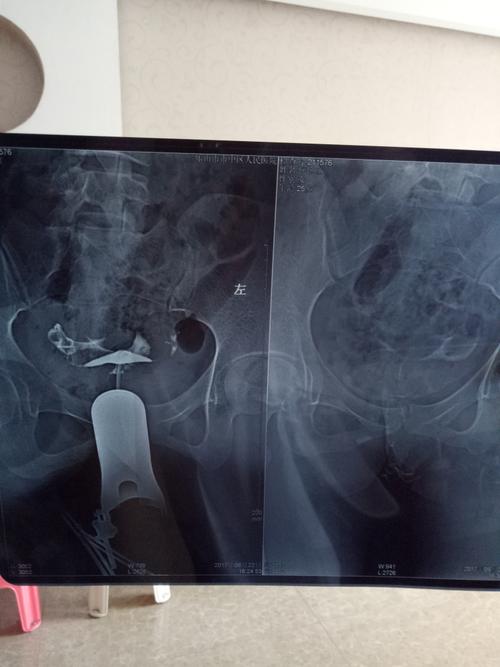

1、输卵管的伞端有粘连,并不是一个很好的状态,一般女性在卵子从卵巢排出的时候,如果到了输卵管表面,受精卵就会着床于输卵管壁上,这个时候,输卵管很容易发生粘连,这样的情况就叫做输卵管伞端粘连。

2、还有一部分女性发生输卵管伞端粘连后,会在输卵管内部发生粘连,会直接造成输卵管管腔被堵塞,这样的话就会发生了炎症,而且输卵管输卵管伞端粘连是一种病变,这个时候输卵管的周围就会受到影响,从而导致受影响的出现粘连。